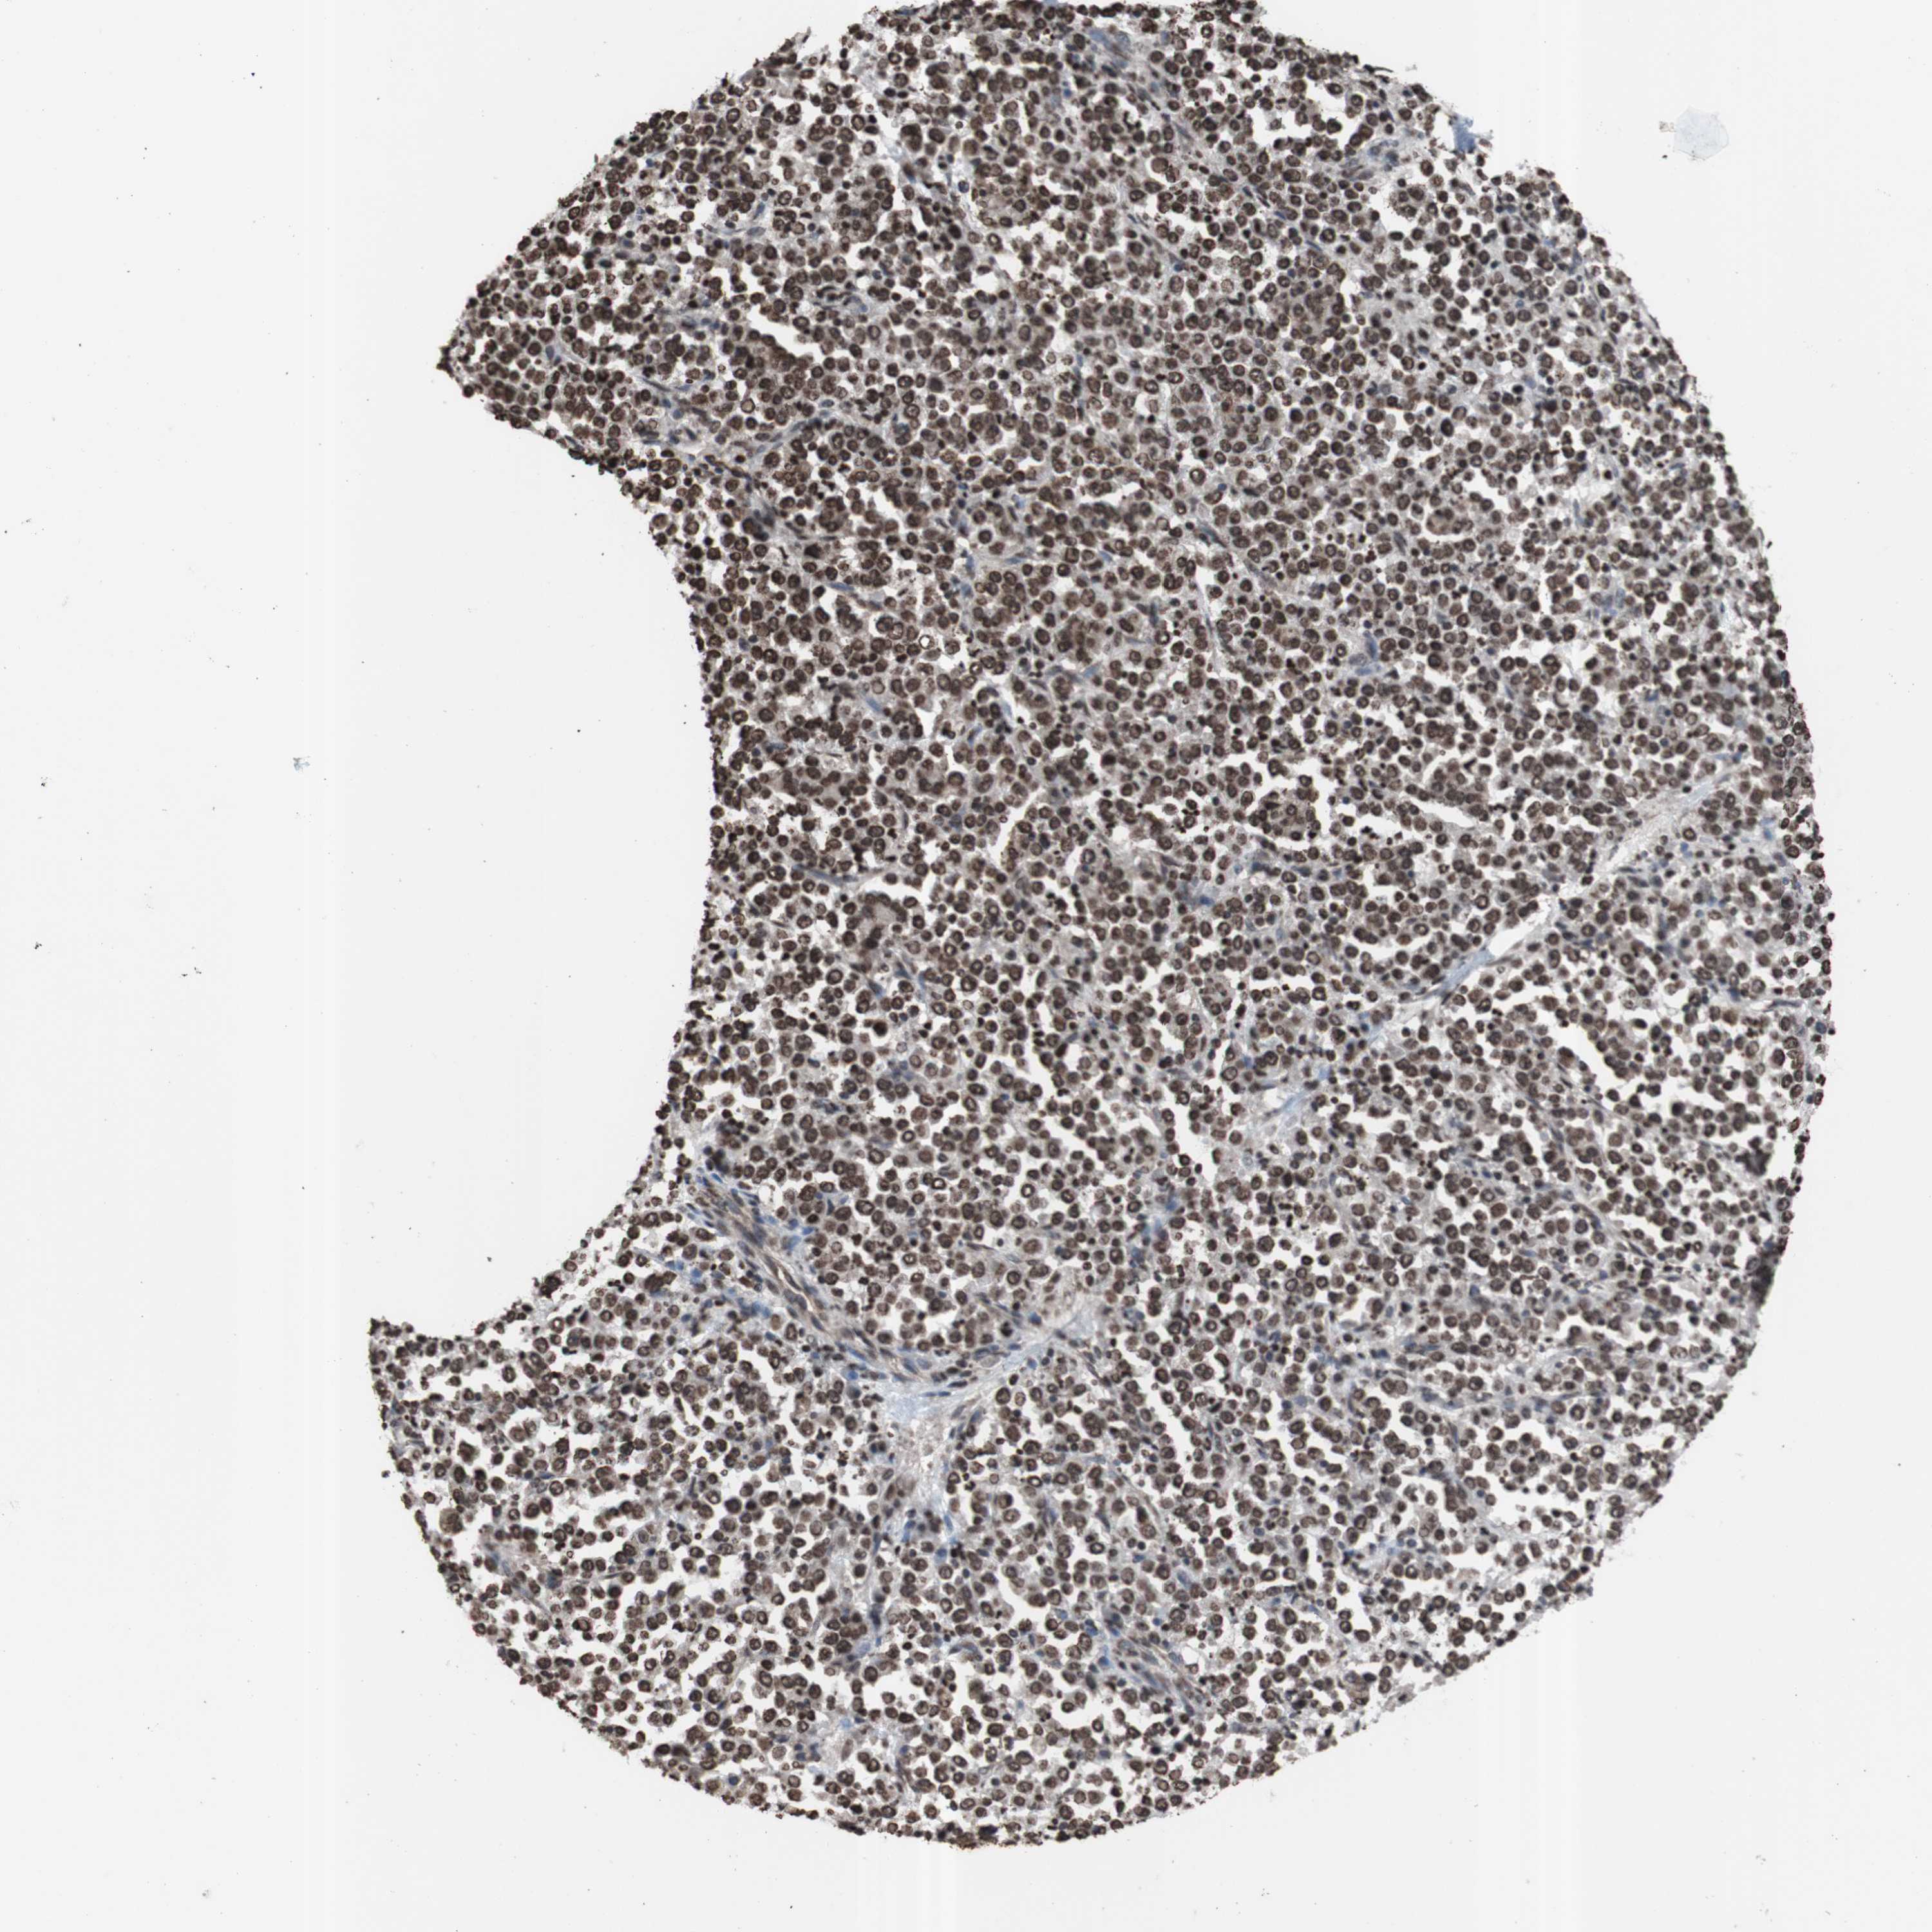

STOMACH CANCER - Protein expressioni

A mouse-over function shows sample information and annotation data. Click on an image to view it in a full screen mode. Samples can be filtered based on level of antibody staining by selecting one or several of the following categories: high, medium, low and not detected. The assay and annotation is described here.

Antibody stainingi

Antibody staining in the annotated cell types in the current human tissue is reported as not detected, low, medium, or high, based on conventional immunohistochemistry profiling in selected tissues. This score is based on the combination of the staining intensity and fraction of stained cells.

Each image is clickable and will lead to virtual microscopy that enables deeper exploration of all samples and also displays staining intensity scores, fraction scores and subcellular localization as well as patient and tissue information for each sample.

Antibody CAB011671

Staining

High

Medium

Low

Not detected

Intensity

Strong

Moderate

Weak

Negative

Quantity

>75%

75%-25%

<25%

None

Location

Nuclear

Cytoplasmic/membranous

Cytoplasmic/membranous,nuclear

Adenocarcinoma, NOS

Adenocarcinoma, High grade